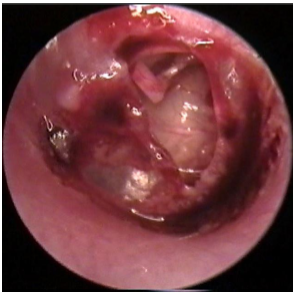

cholesteatoma

Hemotympanum

Traumatic TM perf